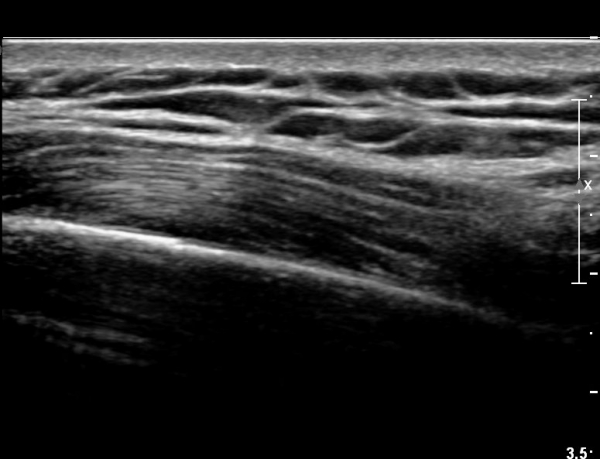

8¹øÂ° °¥ºñ»À ¾ÕÂÊ  Á¾´Ü¸é°Ë»ç»ó  Æ¯ÀÌ ¼Ò°ßÀ» º¸ÀÌÁö ¾ÊÀ¸¸¶(»çÁø 4)